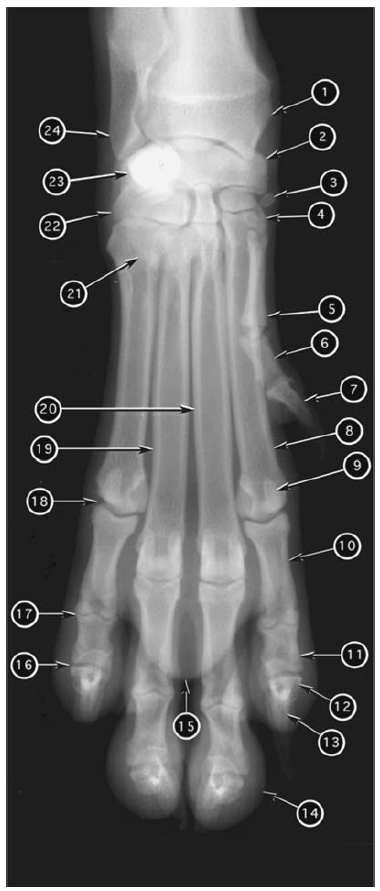

Dorsopalmar radiograph of canine manus

What number?

- Accessory carpal bone

- Carpal pad

- Ulnar carpal bone

- Intermedioradial carpal bone

- Sesamoid bone of abductor pollicis longus

- First carpal bone

- Distal epiphysis (styloid process) of ulna

- Distal epiphysis of radius

- Metacarpal pad

- Metacarpal bone 1

- Second metacarpal bone

- Third metacarpal bone

- Fourth metacarpal bone

- Proximal phalanx of digit 1

- Distal phalanx of digit 1

- Proximal phalanx of digit 2

- Middle phalanx of digit 2

- Unguicular (ungual) process of distal phalanx of digit 2

- Unguicular (ungual) crest of distal phalanx of digit 2

- Abaxial proximal sesamoid bone of digit 2

- Digital pad of digit 3

- Proximal interphalangeal joint of digit 5

- Distal interphalangeal joint of digit 5

- Metacarpophalyngeal joint of digit 5

A

1. Distal epiphysis of radius

2. Intermedioradial carpal bone

3. Sesamoid bone of abductor pollicis longus

4. First carpal bone

5. Metacarpal bone 1

6. Proximal phalanx of digit 1

7. Distal phalanx of digit 1

8. Second metacarpal bone

9. Abaxial proximal sesamoid bone of digit 2

10. Proximal phalanx of digit 2

11. Middle phalanx of digit 2

12. Unguicular (ungual) crest of distal phalanx of digit 2

13. Unguicular (ungual) process of distal phalanx of digit 2

14. Digital pad of digit 3

15. Metacarpal pad

16. Distal interphalangeal joint of digit 5

17. Proximal interphalangeal joint of digit 5

18. Metacarpophalyngeal joint of digit 5

19. Fourth metacarpal bone

20. Third metacarpal bone

21. Carpal pad

22. Ulnar carpal bone

23. Accessory carpal bone

24. Distal epiphysis (styloid process) of ulna